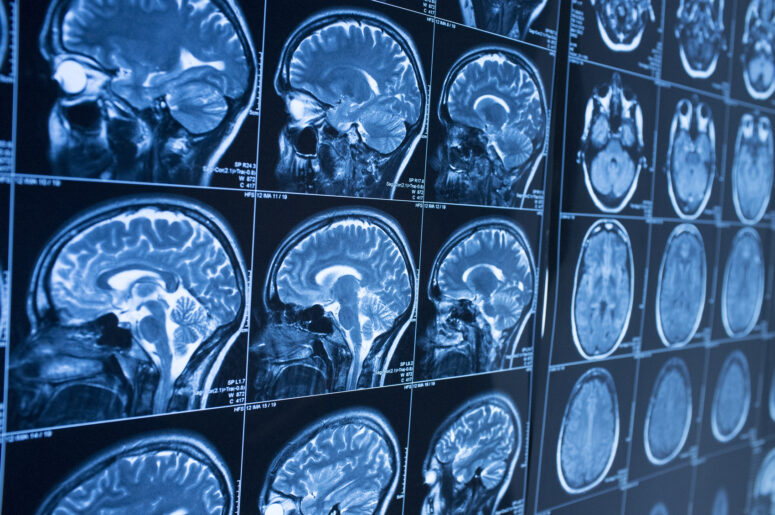

There are two main types of brain injuries: open and closed. Open brain injuries refer to an individual’s skull being fractured. However, the skull is not fractured in a closed brain injury. Closed brain injuries may involve the swelling of the brain and the possibility of blood clots in the skull. Yet, regardless of the type, paralysis, unconsciousness and death can result from a brain injury.

An individual suffering a brain injury after an accident could receive compensation for treatment of the injury and rehabilitation. When individuals seek compensation for their brain injury, they should have a medical evaluation, which can help assess the full extent of the brain damage.